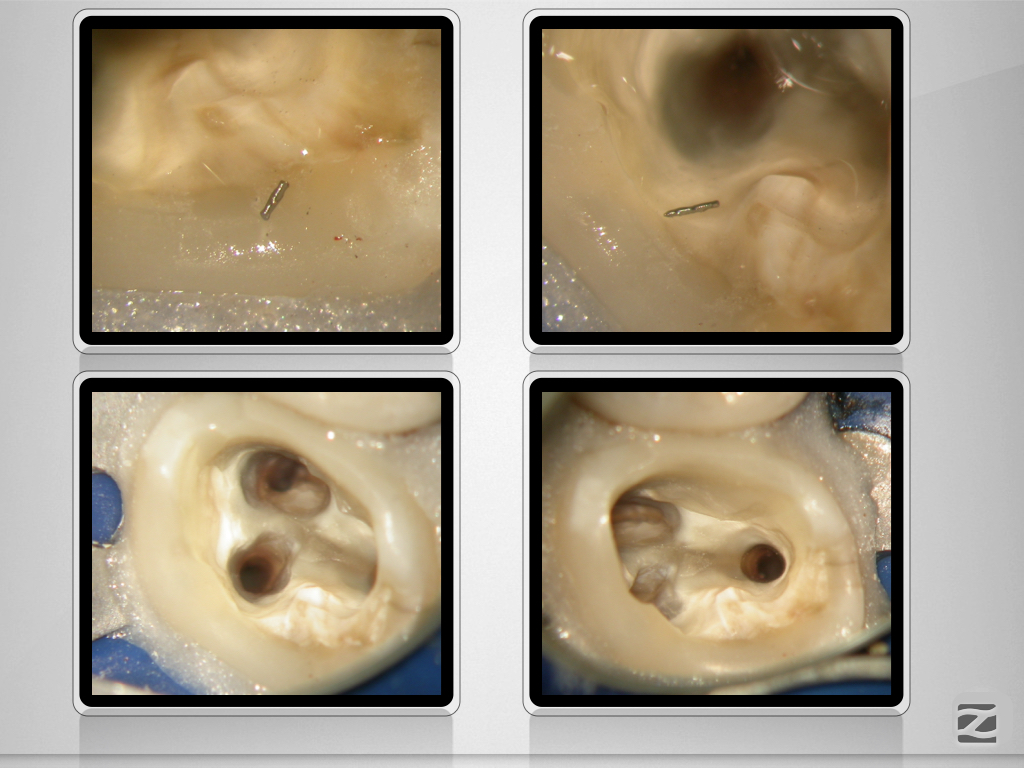

27D.007

Praxistauglicher Kompromiss